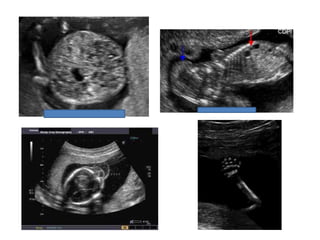

Amniotic band sequence:

Amniotic band sequence refers to a highly variable

spectrum of congenital anomalies that occur in

association with amniotic bands

Amniotic band sequence: Amnioticband sequence refers to a highly variable spectrum of congenital anomalies that occur in association with amniotic bands The estimated incidence of ABS ranges from 1:1200 to 1:15,000 in live births, and 1:70 in stillbirths

Anomalies include: Craniofacial abnormalities— eg, encephalocele, exencephaly, clefts, which are often in unusual locations; anencephaly. Body wall defects (especially if not in the midline), abdominal or thoracic contents may herniate through a body wall defect and into the amniotic cavity. Limb defects — constriction rings, amputation, syndactyly, clubfoot, hand deformities, lymphedema distal to a constriction ring. Visceral defects — eg, lung hypoplasia. Other — Autotransplanted tissue on skin tags, spinal defects, scoliosis, ambiguous genitalia, short umbilical cord due to restricted motion of the fetus